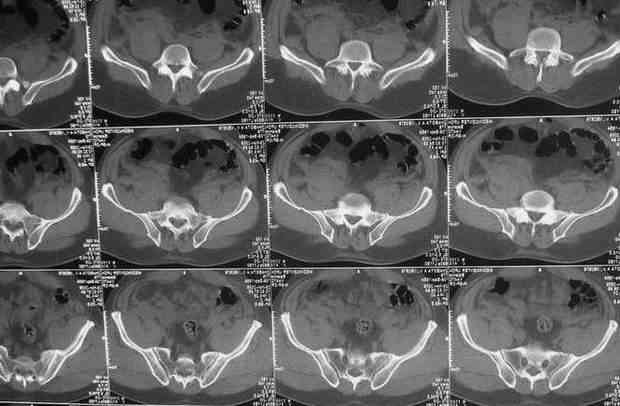

Уважаемые коллеги.У больного оскольчатые переломы левых лонной и седалищной костей со смещением, разрывом симфиза и распространением линии перелома на вертлужную впадину; переломы крыла левой подвздошной кости и правой боковой массы крестца без смещения; разрыв уретры.За последние годы пациент 6 раз оперирован на передней брюшной стенке (гнойный аппендицит срединным доступом, вентральная послеоперационная грыжа и паховые грыжи с обеих сторон, оперированные по 2 раза каждая). Остались 3 грубых втянутых рубца после этих операций. В настоящее время имеются 2-сторонние паховомошоночные грыжи (на одной из КТ-грамм указаны стрелками), из которых левая - значительных размеров. Мошонка огромная, однако, не напряженная. Состояние больного на сегодняшний день относительно удовлетворительное, кровопотеря компенсирована, мочевой пузырь катетеризирован.Прошу мнения сообщества по следующим вопросам: выполнять ли в таких условиях остеосинтез? Если да, то в какой последовательности (отдельно или одним этапом с герниотомией)? Объем остеосинтеза? Доступ?

Доброго времени суток, Сергей. В данном случае фиксация переднего полукольца желательна, так как имеется разрыв уретры (вероятнее всего его мембранозного отдела). Иными словами, нужно восстановить тазовую диафрагму. Доступ - надлобковый в сочетании с неполным подвздошно-паховым доступом по Letournel слева. Нет необходимости в полной визуализации внутренней подвздошной ямки, а, следовательно, и в отсечении мышц от гребня подвздошной кости. Напротив, тщательное выделение элементов в передних отделах создаст благоприятные условия, как для синтеза, так и для герниопластики. После выделения и остеосинтеза (реконструктивная пластина 3-4 отверстия справа и до внутренней подвздошной ямки - слева) выполнить герниотомию. Грыжи рецидивирующие и скорее всего без пластики (к примеру по Lichtenstein) не обойтись. Да, если выполнены уретрограммы и имеется полный отрыв уретры или повреждена ее значительная часть, то нужно определиться с цистостомией. Перкутанная эпицистостомия в послеоперационном периоде будет более предпочтительна. В задних отделах вертикальной нестабильности нет.